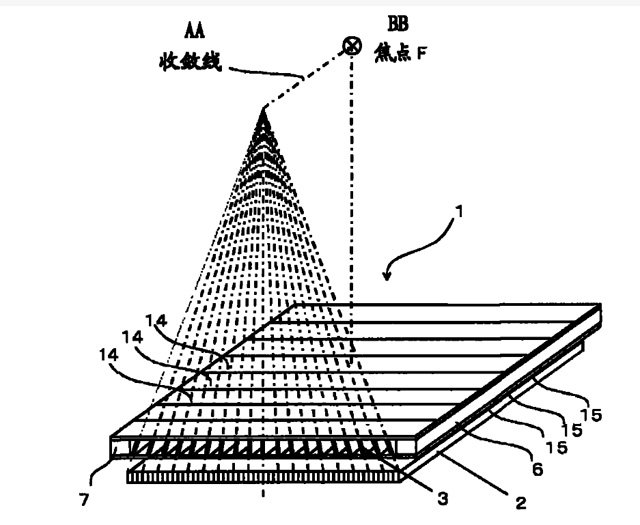

焦距(f):断面看铅条延长线会聚点到栅板垂直距离,即栅板焦距(半径)。栅密度(N):每厘米范围内含有的铅条数,一般40~65线/cm。栅比(R):铅条高度与栅条间隙之比,比值越高滤除散射线能力越强,一般8:1~14:1之间。结构组成:3~5mm薄板,用0.05~0.1mm铅条,夹持在铝或纸之间平行或按斜率排列,相邻铅条间用易透X线物质填充定位、黏合,如木、纸、铝片等。

放置方面:置于人体与片盒间,聚焦面朝向X线入射方向,X线焦点放铅条会聚线上,不能反置,X线中心对准滤线栅中心,左右偏移不超3cm,倾斜X线管要与铅条排列方向平行。摄影时焦距改变不超焦距的25%;活动式滤线器运动时间至少长于曝光时间的1/5;因吸收原发射线要适当增加曝光条件;四肢薄位置一般不用滤线栅;不同千伏对应不同栅比;立位胸片架、乳腺DR摄影等有各自特定滤线栅要求。